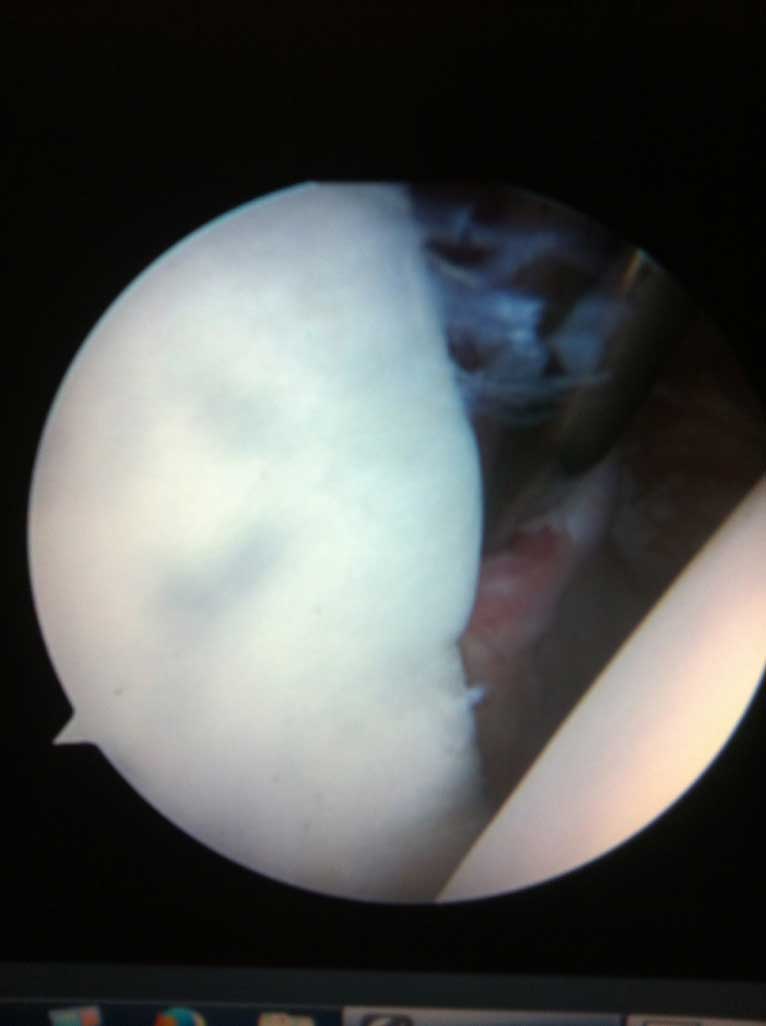

Wie auf der Bilddokumentation ersichtlich, wird die Kontaktfläche zwischen der kleinen knöchernen Pfanne und dem Kopf durch einen knorpeligen Ring, s.g. Labrum, der sich am Pfannenrand befindet, vergrössert.

Das eigentliche Schultergelenk besteht aus 2 knöchernen Partnern, dem Oberarmkopf und der Gelenkpfanne, welche ein Teil des Schulterblattes ist. Dank der sehr flachen und eher kleinen Pfanne und wesentlich grösserem Kopf ermöglich die knöcherne Zusammensetzung des Gelenkes ein sehr grosses Bewegungsausmaß desselben.

Sowohl der Oberarmkopf als auch die Gelenkpfanne sind im Bereich der Gelenkfläche mit einem hyalinen Gelenkknorpel überzogen.